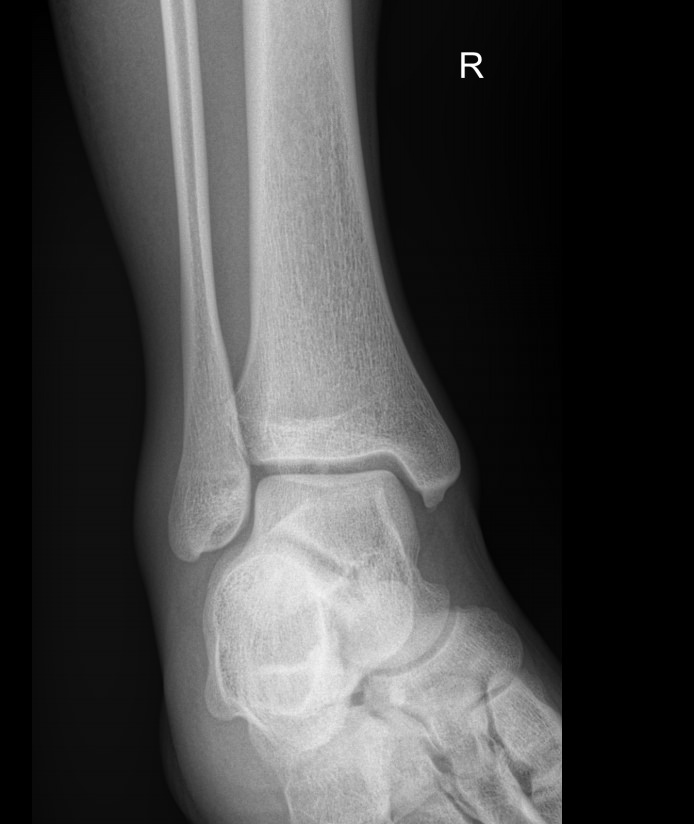

Сустав, соединяющий голень и стопу, наряду с коленным, выполняет важные функции перемещения тела в пространстве и поднятия собственного веса. Голеностоп имеет сложное строение и, как и любой другой сустав в теле человека, подвержен системным заболеваниям и травмам.

В диагностике патологий голеностопных суставов рентгеновское исследование относится к скрининговым, то есть первичным, методам. Действительно, рентген ― классический, простой, доступный и безболезненный способ получить информацию о внутреннем строении и патологических изменениях, произошедших в суставе. А благодаря современным цифровым аппаратам исследование становится и практически безопасным, так как несет минимальную дозу облучения.

В описании врач указывает патологические изменения, если они есть в следующих образованиях:

• Суставные щели;

• Соответствие друг другу суставных поверхностей;

• Костная ткань и надкостница;

• Мягкие ткани.

Также подробно описываются переломы, вывихи, новообразования, их местоположение и особенности.